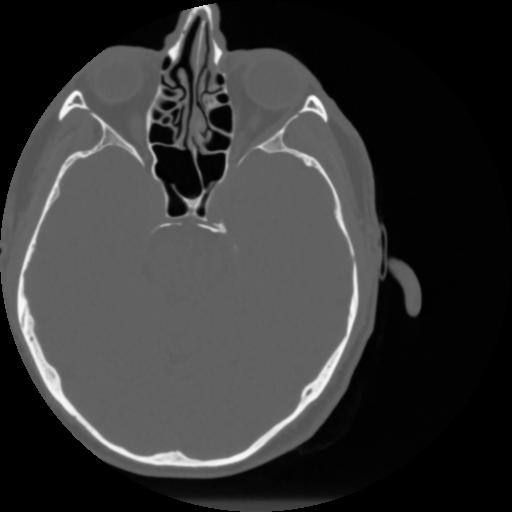

4 CEREBRO,,Vol,0.5,CEREBRO,,